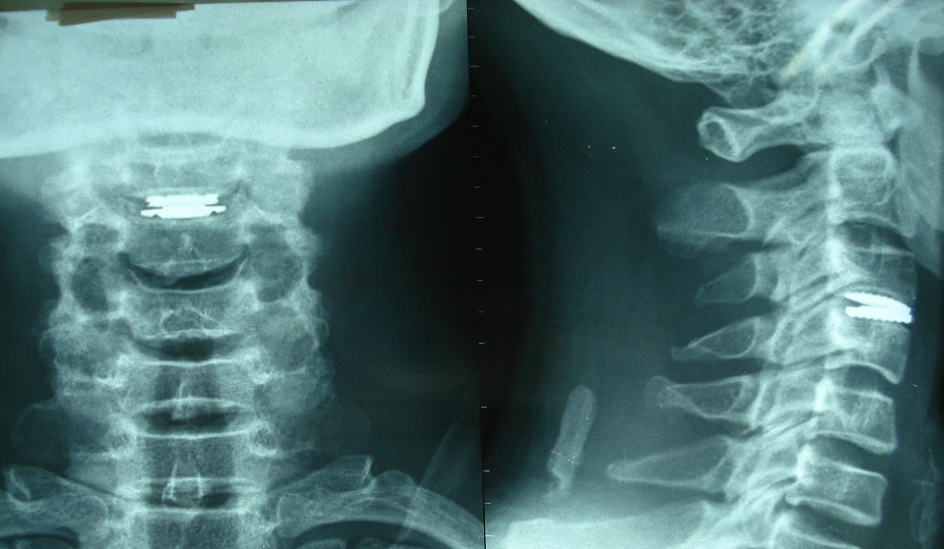

.jpg)

Hình 4.1. Chụp X quang kiểm tra khi bệnh nhân ra viện

Vị trí đĩa đệm nhân tạo: Trong nghiên cứu của chúng tôi, khi kiểm tra lại 6 đĩa đệm nhân tạo được thay, chúng tôi không gặp trường hợp nào đĩa đệm nhân tạo di lệch khỏi vị trí khi được đặt, và không có trường hợp nào lún đĩa đệm nhân tạo vào trong xương thân đốt.

Mất vững cột sống cổ: Không có trường hợp nào được ghi nhận mất vững CSC trên phim X - quang. Về mặt lý thuyết, tình trạng mất vững cột sống cổ có thể do nguyên nhân thoái hóa tăng lên hoặc can thiệp phá vỡ cấu trúc dây chằng vốn có làm mất vững sau mổ. Song, trong NC này, chúng tôi lựa chọn kỹ thuật thay đĩa đệm nhân tạo có khớp, do đó buộc phải loại trừ là trường hợp mất vững CSC, đồng thời, phẫu thuật thay đĩa đệm chỉ can thiệp trên 1 tầng đĩa đệm là một phẫu thuật ít xâm lấn, vì vậy mất vững sau phẫu thuật thường có tỷ lệ nhỏ. Tuy nhiên, tỷ lệ mất vững CSC sau phẫu thuật là bằng không trong NC của chúng tôi vẫn chưa có giá trị khẳng định được là thay đĩa đệm nhân tạo sẽ không làm mất vững CSC do cỡ mẫu nghiên cứu của chúng tôi chưa thật đủ lớn và thời gian theo dõi chưa đủ dài.